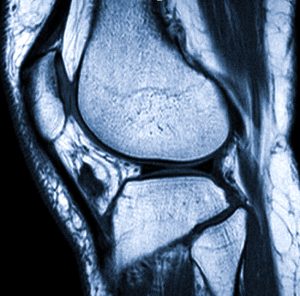

Диагностика основана на сборе анамнеза, местном осмотре. Из инструментальных методов информативно МРТ, УЗИ, артроскопия (но это операция и выполняется она по показаниям, при блокаде сустава).